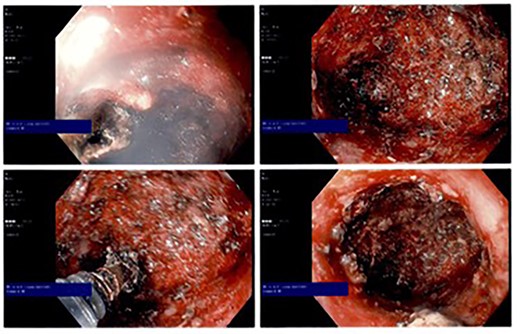

The patient was placed in the prone jackknife position and a digital exam was performed by probing the punctate perineal wound with noted purulent drainage. The area was digitally dilated up to an area of apparent stenosis 3–4 cm into the tract which, using a probe, was noted to track up about 12 cm proximally. An esophagogastroduodenoscopy scope was then passed through the opening to view the cavity, which was roughly 3 cm in diameter and 12 cm in length. Using hot biopsy forceps and hot snare, the inner lining of the cavity was debrided with electrocautery (Fig. 3). All cavity surfaces were cauterized as able including the neck of the cavity. The cavity was then irrigated with hydrogen peroxide and a 30-French Malecot drain was placed in the opening and secured to the skin with a 2-0 silk suture.

Intraoperative endoscopic photographs showing cauterized cavity epithelium.